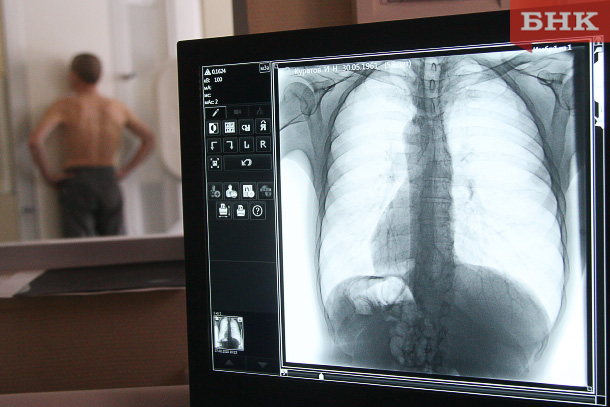

Все случаи повреждения легких описаны у молодых людей, сообщила Ольга Курочкина. Средний возраст пациентов — от 20 до 25 лет. «Именно молодые потребители электронных сигарет и вейпов находятся в группе риска», — подчеркнула врач.